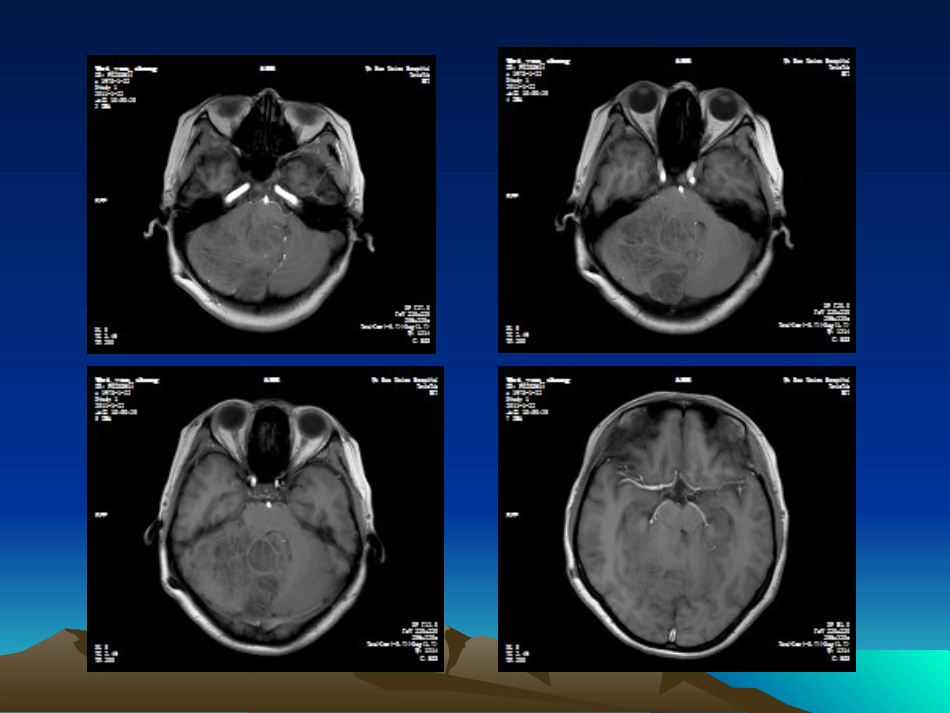

CASECASE男性,33岁,行走不稳三天小脑发育不良性节细胞瘤•罕见的小脑良性占位性病变•起自小脑皮层、缓慢进展•WHO分类:神经元和混合神经元、神经胶质肿瘤,Ⅰ级良性肿瘤•性质、发病机制和遗传学改变尚不完全清楚,是原发肿瘤、发育畸形或是错构瘤性病变仍有争论•发病年龄从新生儿至74岁不等,以10~30岁者多见,平均为34岁;无性别差异•小脑半球和中线均可发生•常见症状体征:第四脑室或中脑导水管受压引起梗阻性脑积水所致的颅压增高和后颅窝占位表现•40%伴有Cowden综合征病理特征病理特征•①弥漫或局限性小脑皮质增生,累及一侧或两侧小脑半球甚至小脑蚓部,病变侧中央白质一定程度的减少;•②大体见分子层苍白、增厚,间有有髓纤维;浦肯野细胞层缺如,颗粒细胞层增宽并含有大量异常颗粒细胞,其轴突伸入分子层;•③常见钙质沉积于分子层的毛细血管、微血管壁。